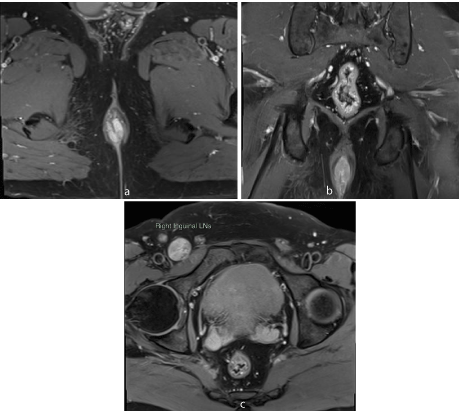

MR imaging revealed short segment circumferential wall thickening of the anal canal with lower margin approximately 1.7cm from anal verge. It was nearly 3 cm in length and 7mm in maximum thickness. The wall thickening showed hyperintense signal in T1-weighted images and T2-weighted images (Figures 1-3). Restricted diffusion with corresponding low signal in ADC map was noted figure 4. Post gadolinium T1-weighted fat saturated images showed hyper enhancement of the wall thickening (Figure 5). The thickening was involving the internal sphincter. No invasion of intersphincteric plane and external sphincter was noted. No extension into perianal fat was noted. Few enlarged heterogenously enhancing lymph nodes were noted in right inguinal region largest 23 x 21 mm in size. The patient underwent wide local excision with right inguinal dissection and adjuvant loco-regional radiotherapy. The histopathological examination showed features suggestive of primary anal malignant melanoma (Figure 6). In routine follow up, the patient showed no features of local recurrence or distant metastasis.

Figure 5: Axial (a) and coronal (b) post gadolinium T1-weighted fat saturated MR image shows enhancing wall thickening and associated right inguinal lymphadenopathy (c).